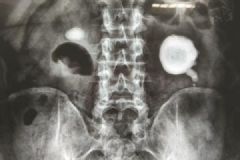

男子左肾长出“荷包蛋”结石:频加班爱喝浓茶[多图]

肾结石是泌尿系统比较常见的疾病,和个人的饮食生活习惯有很大的联系,一般来说,喝水少是造成肾结石的原因之一,恩施的一名男性加班比较频繁,而且爱喝浓茶,喝水少,后来...